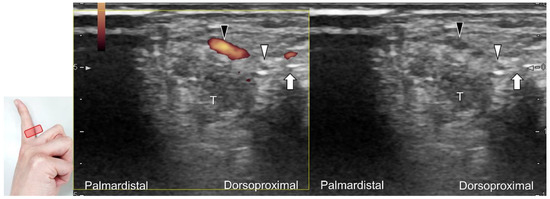

Figure 5. Comparative ultrasonography (long-axis view) between healthy (A) vs. affected (B) sides shows a schwannoma (black arrowhead) with increased intraneural vascularity.

Carpal tunnel syndrome is the most common entrapment neuropathy whereby the median nerve is entrapped by various causes, like hypertrophy of the flexor retinaculum (Figure 2C,D) and compression from the accessory muscles, swollen tendons, ganglions, and bony fractures within the tunnel. Ultrasonographic changes encompass swelling proximal to the entrapment site (Figure 3A), flattening over the entrapment site (Figure 3B), intraneural hypervascularity (Figure 3C), and focal loss of the trimline pattern (Figure 3D).

The nerve’s CSA (a cutoff value of 9–10.5 mm2) arises as the most useful parameter for the diagnosis [28], whereas its diameter, gliding resistance [29], stiffness (evaluated by sonoelastography), and intraneural vascularity (assessed by power Doppler imaging) may serve as adjuvant indicators. A bifid median nerve (Figure 4A), the presence of a persistent median artery (Figure 4B) with or without thrombosis, accessory flexor digitorum superficialis muscle (Figure 4C), laceration of the palmaris longus tendon (Figure 4D), and schwannoma (Figure 5) can be associated findings for carpal tunnel syndrome [9].